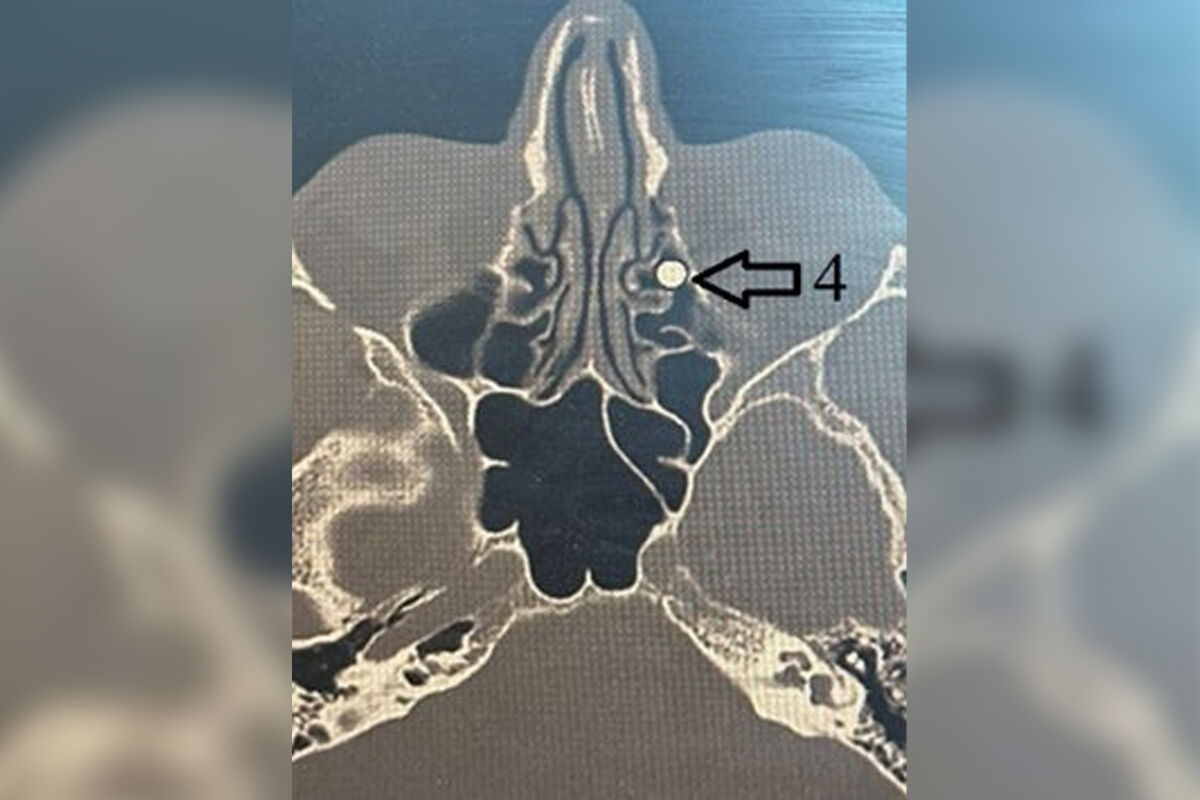

Пациент поступил с ранением из травматического ружья. Пуля диаметром 4,5 мм вошла через внутренний угол глаза, прошла через глазницу и застряла в носу. Сначала мужчине провели операцию по восстановлению тканей глаза, после чего передали пациента врачам лор-отделения клиники.